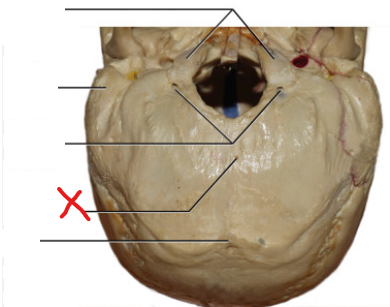

8

Crus cerebri

What does the circled area refer to

Interpeduncular fossa

26

Oculomotor nerve

What are the nerve fibres descending through the crus cerebriÂ

Corticobulbar fibres, corticospinal fibres

What type of fibres are the corticobulbar fibres

Motor fibres